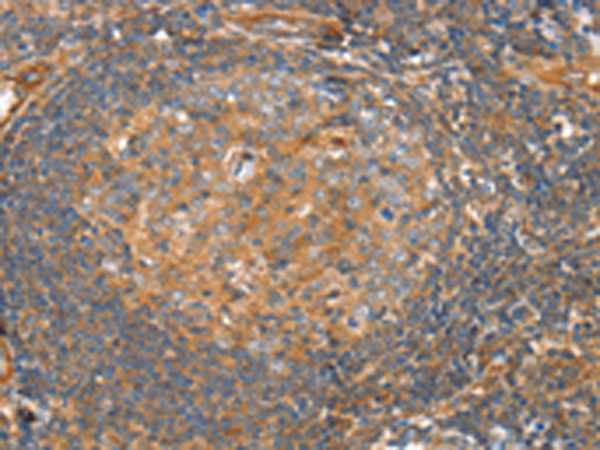

分类: 科研抗体货号: P08787别名: SMUC; SNAIL3; ZNF293; Zfp293应用: IHC反应种属: Human